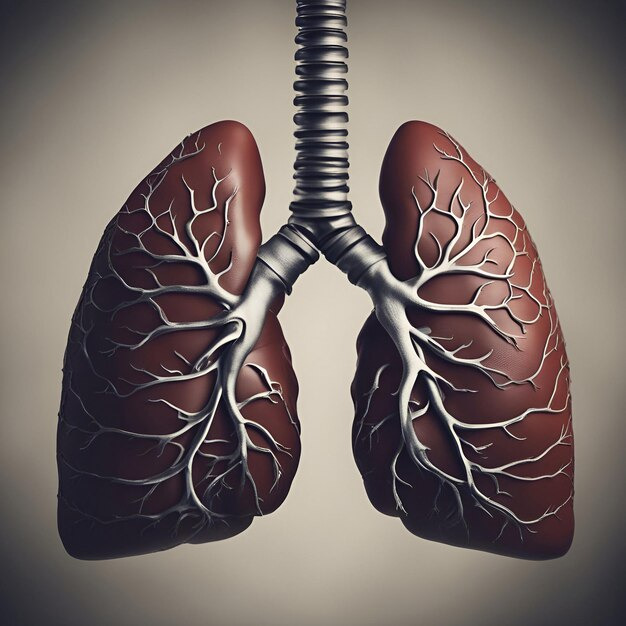

기흉은 폐와 흉막 사이의 마찰로 인해 폐에 구멍이 생겨 폐 속의 공기가 흉막강 내로 새어 나와 폐가 위축되는 질환입니다. 흉막강은 폐를 둘러싼 두 겹의 얇은 막으로 구성되어 있는데, 한 겹은 폐에 직접 부착되어 있고 다른 한 겹은 흉벽에 부착되어 있습니다. 기흉은 외상성 기흉과 자연 기흉으로 나뉘며, 자연 기흉은 다시 일차성 기흉과 이차성 기흉으로 나눌 수 있습니다.

기흉의 원인은 다양합니다. 가장 흔한 원인은 일차성 자연 기흉으로, 10대에서 20대의 젊고 키가 크면서 마른 체형의 남성에게 많이 발생합니다. 이외에도 흡연, 폐결핵, 천식 등의 폐 질환, 대기오염, 미세먼지 등의 환경적 요인이 원인이 될 수 있습니다.

기흉을 예방하기 위해서는 금연이 필수적입니다. 또, 평소에 규칙적인 운동과 건강한 식습관을 유지하고, 스트레스를 관리하는 것이 좋습니다.